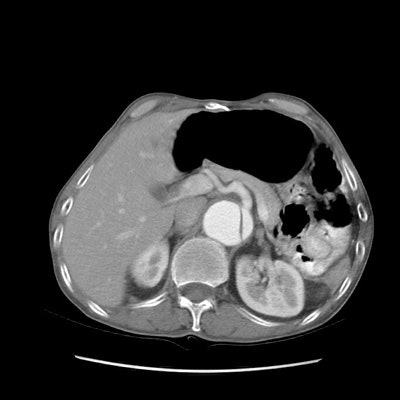

Type B dissection on CT:

The images below demonstrate a Type B aortic dissection beginning at the level of the thoracic outlet (note also aortic aneurysm). Both the superior mesenteric artery and the left renal artery arise from the false lumen. (Click images to enlarge)